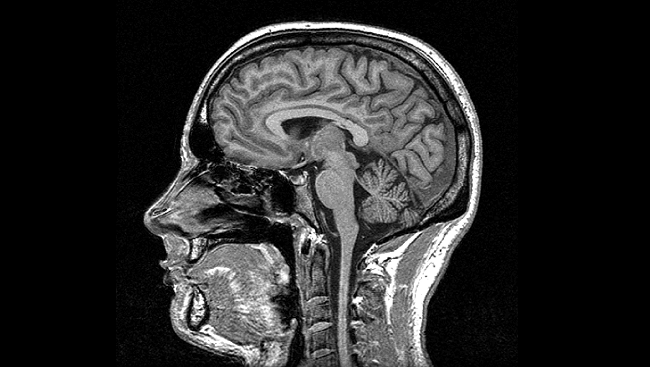

MRI Scan

MRI scanners are a bit like the CT machine, but you lie inside a huge magnet. It uses magnets and radio waves to create an image of the body.

Because of the magnetic field generated, they’re not a suitable imaging technique for patients who have pacemakers or other pieces of ‘metal’ in their bodies – umm, like Body with his keys!

However, because it does not use ionising radiation and can create detailed images of soft tissue, it can be used for the detection of many diseases.

An MRI scanner is like a short tunnel that’s open at both ends, through which a motorised bed passes. During a scan you lie on the bed and a small ‘receiving device’ is placed behind, or around, the part of your body being scanned. You are then moved into the scanner tube, either head-first or feet-first, depending on which part of your body is being scanned.

- MRI scans are painless. However, it is important to be as comfortable as possible during a scan, because you must keep the part of your body being scanned very still to avoid blurring the images.

- A typical scan lasts between 15 and 60 minutes, depending on the size of the area being scanned and how many ‘pictures’ are taken.